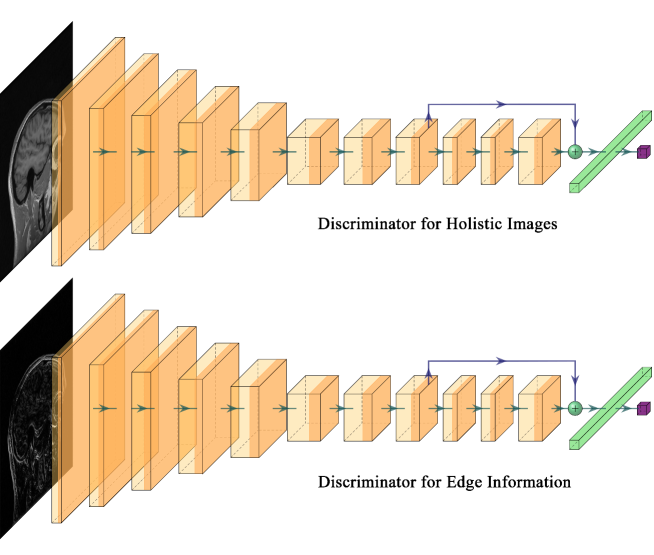

In this work, a first discriminator is used to distinguish the reconstructed MR images from the ground truth MR images , whereas an additional discriminator is designed to assist the reconstruction of the edge information. Edge information is usually extracted by means of a Sobel operator . The edge information of the reconstructed MR image and the edge information of the MR ground truth are fed to , so that the result is counted into the adversarial loss . The new adversarial loss can be defined as follows

where and denote the weights of the discriminator for the holistic image and the edge information correspondingly, and as it will be later discussed.

Traditional GAN trains a single discriminator to compete against the generator. Although it improves reconstruction quality compared with other methods, only integral MR image properties are considered, without enhancing edge details. The current study proposes a dual discriminator GAN for edge information enhancement. The generated MR image and sensitivity-weighted MR ground truth are fed into discriminator for holistic image reconstruction. We use the Sobel operator to extract the edge information from MR images, and input edge information for the reconstructed image and ground truth into . Thus, both holistic image information and edge details can be simultaneously reconstructed.

Fig. 4 shows the common network structure used for both discriminators. First, a cascade of convolution layers with stride = 2 downsamples and extracts MR image features. Two convolution layers and a residual block follow the final convolution layer. The residual block consists of three convolution layers, and input and output are connected by a shortcut. All convolution layers above are followed by a BN layer and Leaky ReLU layer. Finally a full connection layer and a Sigmoid layer output the prediction results. Results of both discriminators are incorporated into the adversarial loss .